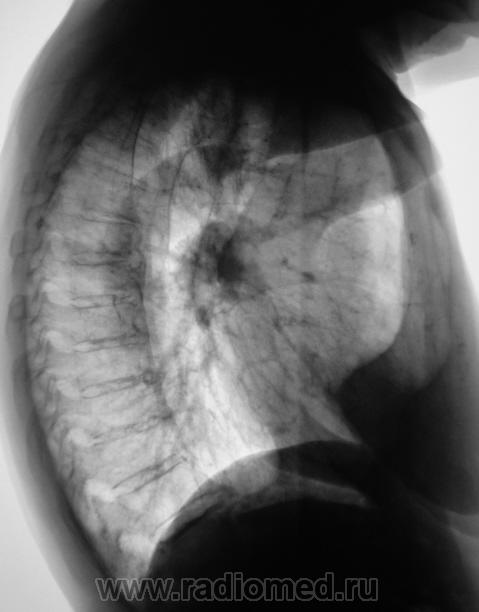

участок инфильтрации в 1 сегменте справа.

В заключении бы написал:Правостороння сегментарная пневмония.

Однако смущает дополнительная тень апикально слева и это похоже на плевральный выпот. Возможно, что снимок сделан с подворотом, хотя не исключаю и патологию.

Подворота нет. У бабульки - сколиоз.

Похоже на рак.

очень похоже... а на туберкулез не похоже?

"Тубер" исключили. Знаменательно то, что, по всей видимости, негативную тенденцию, с непрохождением профилактической флюорографии "победить" невозможно. В 2007 пациентка лежала в терапии. В 2008 "с переломом" лежали в хиругии. Флюорографию "проходила", когда "сама не помнит". Подняли, все, что только можно - по самому малому - 6 лет проф. флюорографии не проходила.